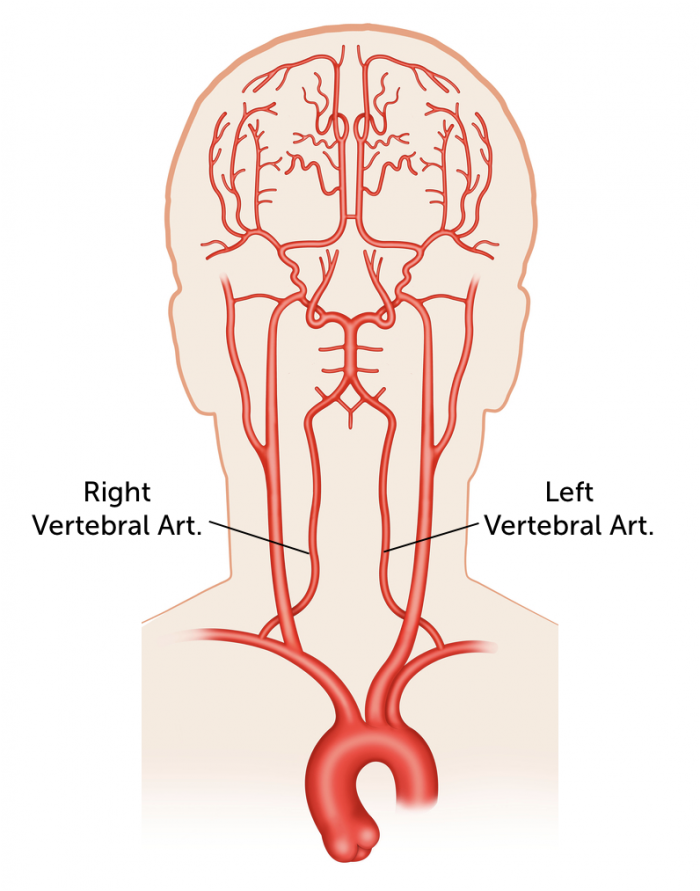

While RBCs normally travel to the lungs, using intra-arterial (IA) catheters, we can direct RBCs loaded with the nanogel to specific organs. Using IA catheters allows the targeting of other organs by injecting the RBC nanogel complex directly into arteries that feed those organs. The arteries that we will target are the vertebral arteries. This is because spinal injections are generally safe procedures. If complications occur, they are usually mild and self-limited. Since blood normally travels to the brain, the RBC will have no problem getting through the BBB and getting to the brain.